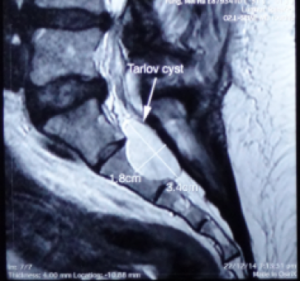

Usually incidental finding in lumbar MRI, one or more Tarlov Cysts will be found in the sacral spinal canal. If they are smaller than 1cm, the patient may not have any symptoms. But if the tarlov cyst grow to more than 1.5cm and it compressed the nerve, this may cause discomfort in patient.

Tarlov cyst generally find at the first to the third section of the sacrum and is filled with cerebrospinal fluid. The swelling can gradually increase and cause the cauda equina nerve to be compressed, causing nerve root inflammation or myelopathy and even affecting the bony structures. Magnetic resonance imaging can clearly distinguish the location, size, and relationship with the dura and nerve roots of the sacral canal.